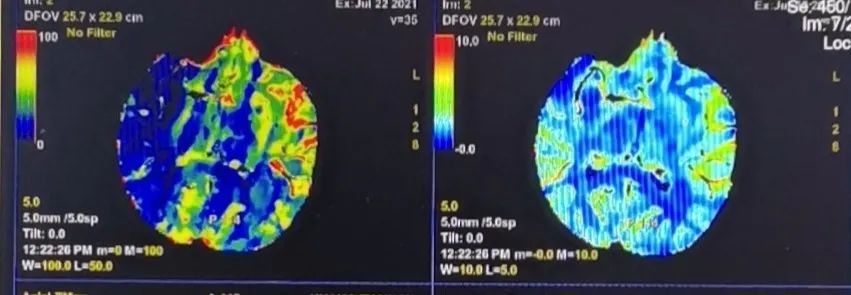

CTA:右侧大脑中M1闭塞。

CTP:右侧大脑半球广泛缺血,梗死体积22ml,半暗带体积130ml